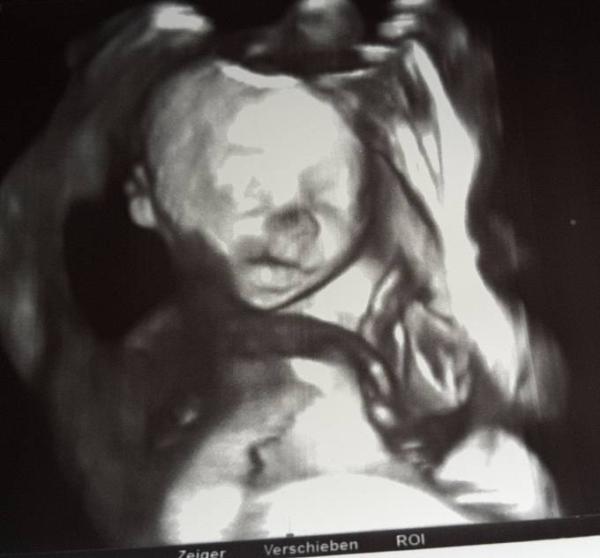

Huhu, ich hatte heute meinen nächsten Termin. Der Eisenwert ist von 11,1 vor 4 Wochen wieder auf 13,9 gestiegen. Das Mittel habe ich nach 2 Tagen gegen Hohes C Plus Eisen ausgetauscht. Scheint geholfen zu haben. Die Maus ist mittlerweile 30 cm groß und 600 gr schwer. Er ist super zufrieden, aber mein Gebärmutterhals ist seit den letzten 4 Wochen schon 1 cm kürzer geworden. Also nix mit Übungswehen. Muss jetzt ins Krankenhaus, um zu gucken, wie es weitergeht. Magnesium hab ich heute auf der Arbeit von einer Pharmarefferentib geschenkt bekommen, das kommt jetzt zum Einsatz. Da es schon Kind Nr. 6 ist, geht halt alles was schneller. Aber bis kurz nach Weihnachten sollte die Maus schon drin bleiben. Zum Glück tut es mir nicht immer weh, sondern nur, wenn ich Stress habe. Zum Glück bin ich relativ stressresitent. Ich denke eher, die Verkürzung kommt vom Husten, der jetzt immerhin schon 7Wochen anhält. Ich hoffe, es geht euch gut

Hier noch ein 3D Bild, was es heute auch gab. Der Zuckertest war übrigens auch ganz super.